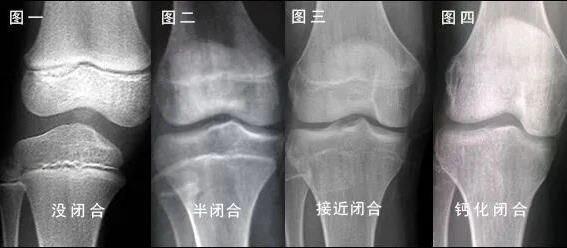

一图读懂骨骺闭合

如果实在不死心,也可以再拍一个膝关节的X光片,看看股骨和胫、腓骨的成长板是否还存在。因为手骨和膝关节部位的成长板闭合时间基本一致,一旦膝关节部位的成长板闭合,一般身高就基本停止生长了。

膝关节正位片

骨骺线一旦完全闭合,身高就停止生长了。